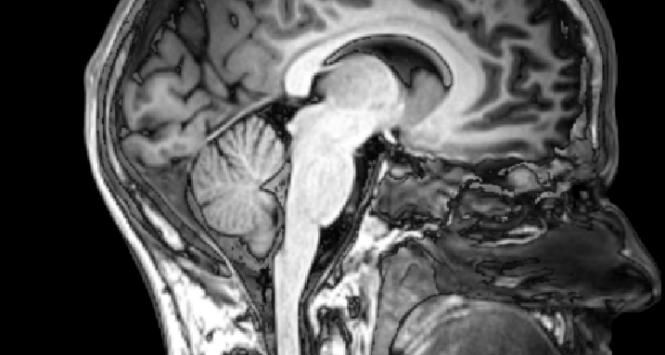

mózg

Co wiemy o mózgu

W ostatnich latach na temat funkcjonowania mózgu dowiedzieliśmy się znacznie więcej niż przez kilka poprzednich stuleci. Ale wciąż towarzyszy nam dramatyczne pytanie: czy ludzki umysł potrafi zrozumieć jak działa mózg? I czym jest świadomość?